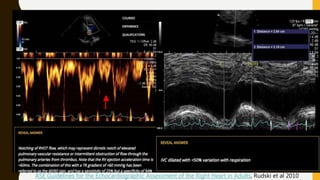

ECHO

ASE Guidelines for the Echocardiographic Assessment of the Right Heart in Adults, Rudski et al 2010

• 60/60 sign: Pulmonary valve acceleration time ≤60ms and

tricuspid regurgitation pressure gradient ≤60mmHg

• Mcconnell's sign {(McCS), described as hypo- or akinesis of

the RV - free wall with preservation of the apex, is

associated with acute pulmonary embolism (aPE)} {Sensitivity of

77%, specificity of 94%}

• Signs of RV pressure overload, defined as 1 or more of the following

signs:

– Right sided cardiac thrombus

– RV diastolic dimension on parasternal view of >30mm or a ratio of

RV to left ventricle of >1

– Systolic flattening of the interventricular septum

– Pulmonary valve acceleration time <90ms or tricuspid regurgitation

pressure gradient >30mmHg in absence of RV hypertrophy

– Tricuspid annular plane systolic excursion(TAPSE) <16 mm